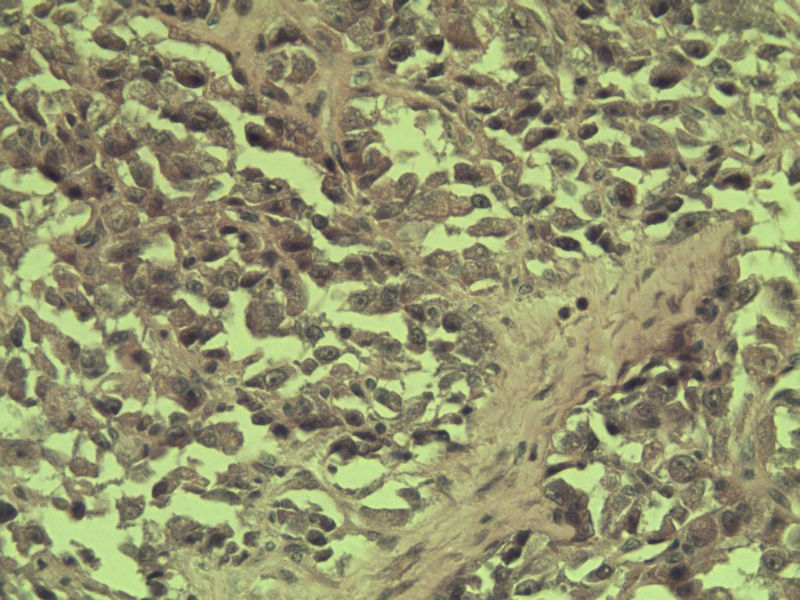

女 70岁 右颈部 头皮 多发皮下结节      取颈部部分结节送检 灰白小组织 1 块,直径 0.4 cm。 请问这个是什么?

肿瘤细胞大,上皮样,核空泡状,核仁明显,胞质嗜酸性或透明。

考虑:恶性黑色素瘤?

近心型上皮样肉瘤?

软组织透明细胞肉瘤?

上皮样多形性脂肪肉瘤?

等免疫组化标记!

此片染色欠佳,取材或切面也有问题,加大了诊断的难度,恶黑确实需要考虑,但其他一些转移癌也需要排除,比如肺癌之类的,还是期待免疫组化!